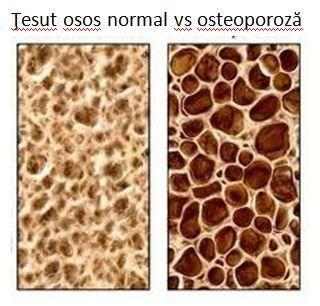

Alimentul care previne depunerea colesterolului pe vasele de sânge și combate osteoporoza